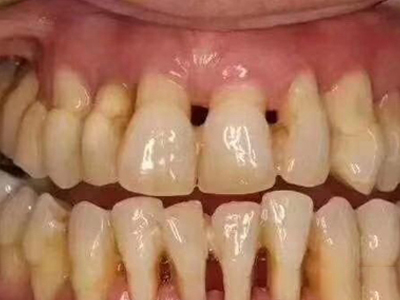

牙龈退缩上排多颗牙的牙根暴露图

牙龈退缩导致上排多颗牙齿的牙龈回缩,部分牙根暴露在外,伴有牙齿松动、口臭等症状,是由于牙周炎、局部受力过大等因素导致。